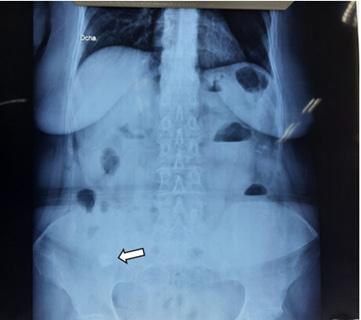

Figura 1. Cuatro formas de língulas mandibulares. Truncada (A), triangular (B), nodular (C) y asimilada (D) (8).

Figura 2. Formas de la língula en mandíbulas adultas secas. Truncada (A), presenta una forma triangular cortada en su vértice. Triangular (B), con vértice dirigido hacia el cóndilo mandibular. Nodular (C). Asimilada (D), no se evidencia la prominencia ósea lingular (8, 9).